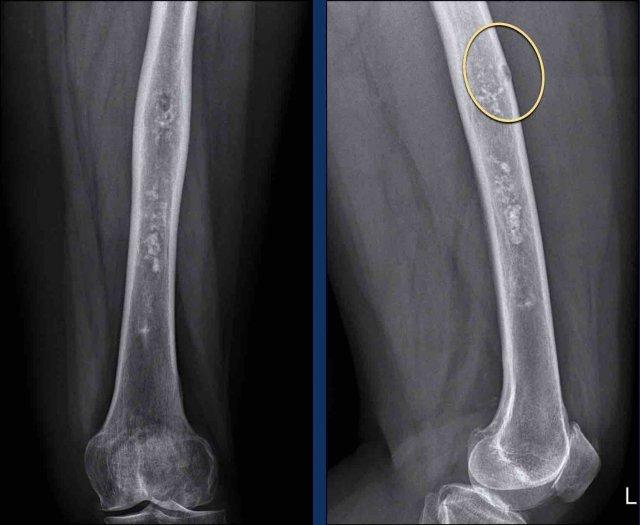

Có một tổn thương đo được hơn 20 cm ở thân xương đùi.

Lưu ý các vôi hóa dạng bỏng ngô trong nền tổn thương.

Có một nốt khu trú (trong vòng tròn màu vàng) gây xói mòn vỏ xương và có sự mở rộng nhẹ của ống tủy xương.

Continue with the MR…

Hình ảnh

Hình ảnh MR cho thấy mô mỡ xen kẽ giữa các nốt sụn.

Có tín hiệu cao trên ảnh T1W mặt phẳng đứng dọc và tín hiệu thấp trên ảnh xóa mỡ (các mũi tên).

Có một nốt khu trú gây lõm vỏ xương (<10%) và có sự mở rộng nhẹ của ống tủy xương.

Kết luận

Tổn thương được chẩn đoán là ACT và vẫn ổn định trong quá trình theo dõi.